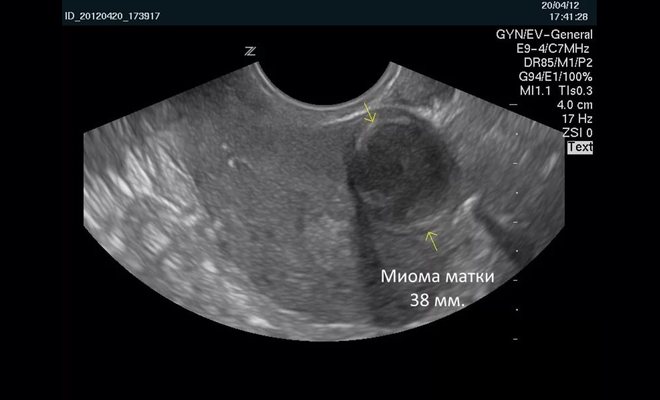

Обычно на фото при УЗИ выявляются увеличенные размеры главного женского органа и возникновение в маточной полости сгустка округлой формы, который, к тому же, хорошо проводит звук. Если матка на фото УЗИ изменила свою форму, значит, миоматозные узлы достигли уже весьма приличных размеров.

Стоит отметить, что миома матки фото на УЗИ будет выглядеть как совершенно иная от матки структура. Размеры ее обычно указываются в неделях беременности, который будет свидетельствовать на самом деле о размере главного женского органа, соответствующего сроку вынашивания ребенка.

Фото 1. Как выглядит миома матки на УЗИ.

Врач-сонолог определяет миому как округлый объект с гетерогенной структурой и чёткими границами, делающими сигнал датчика слабее.